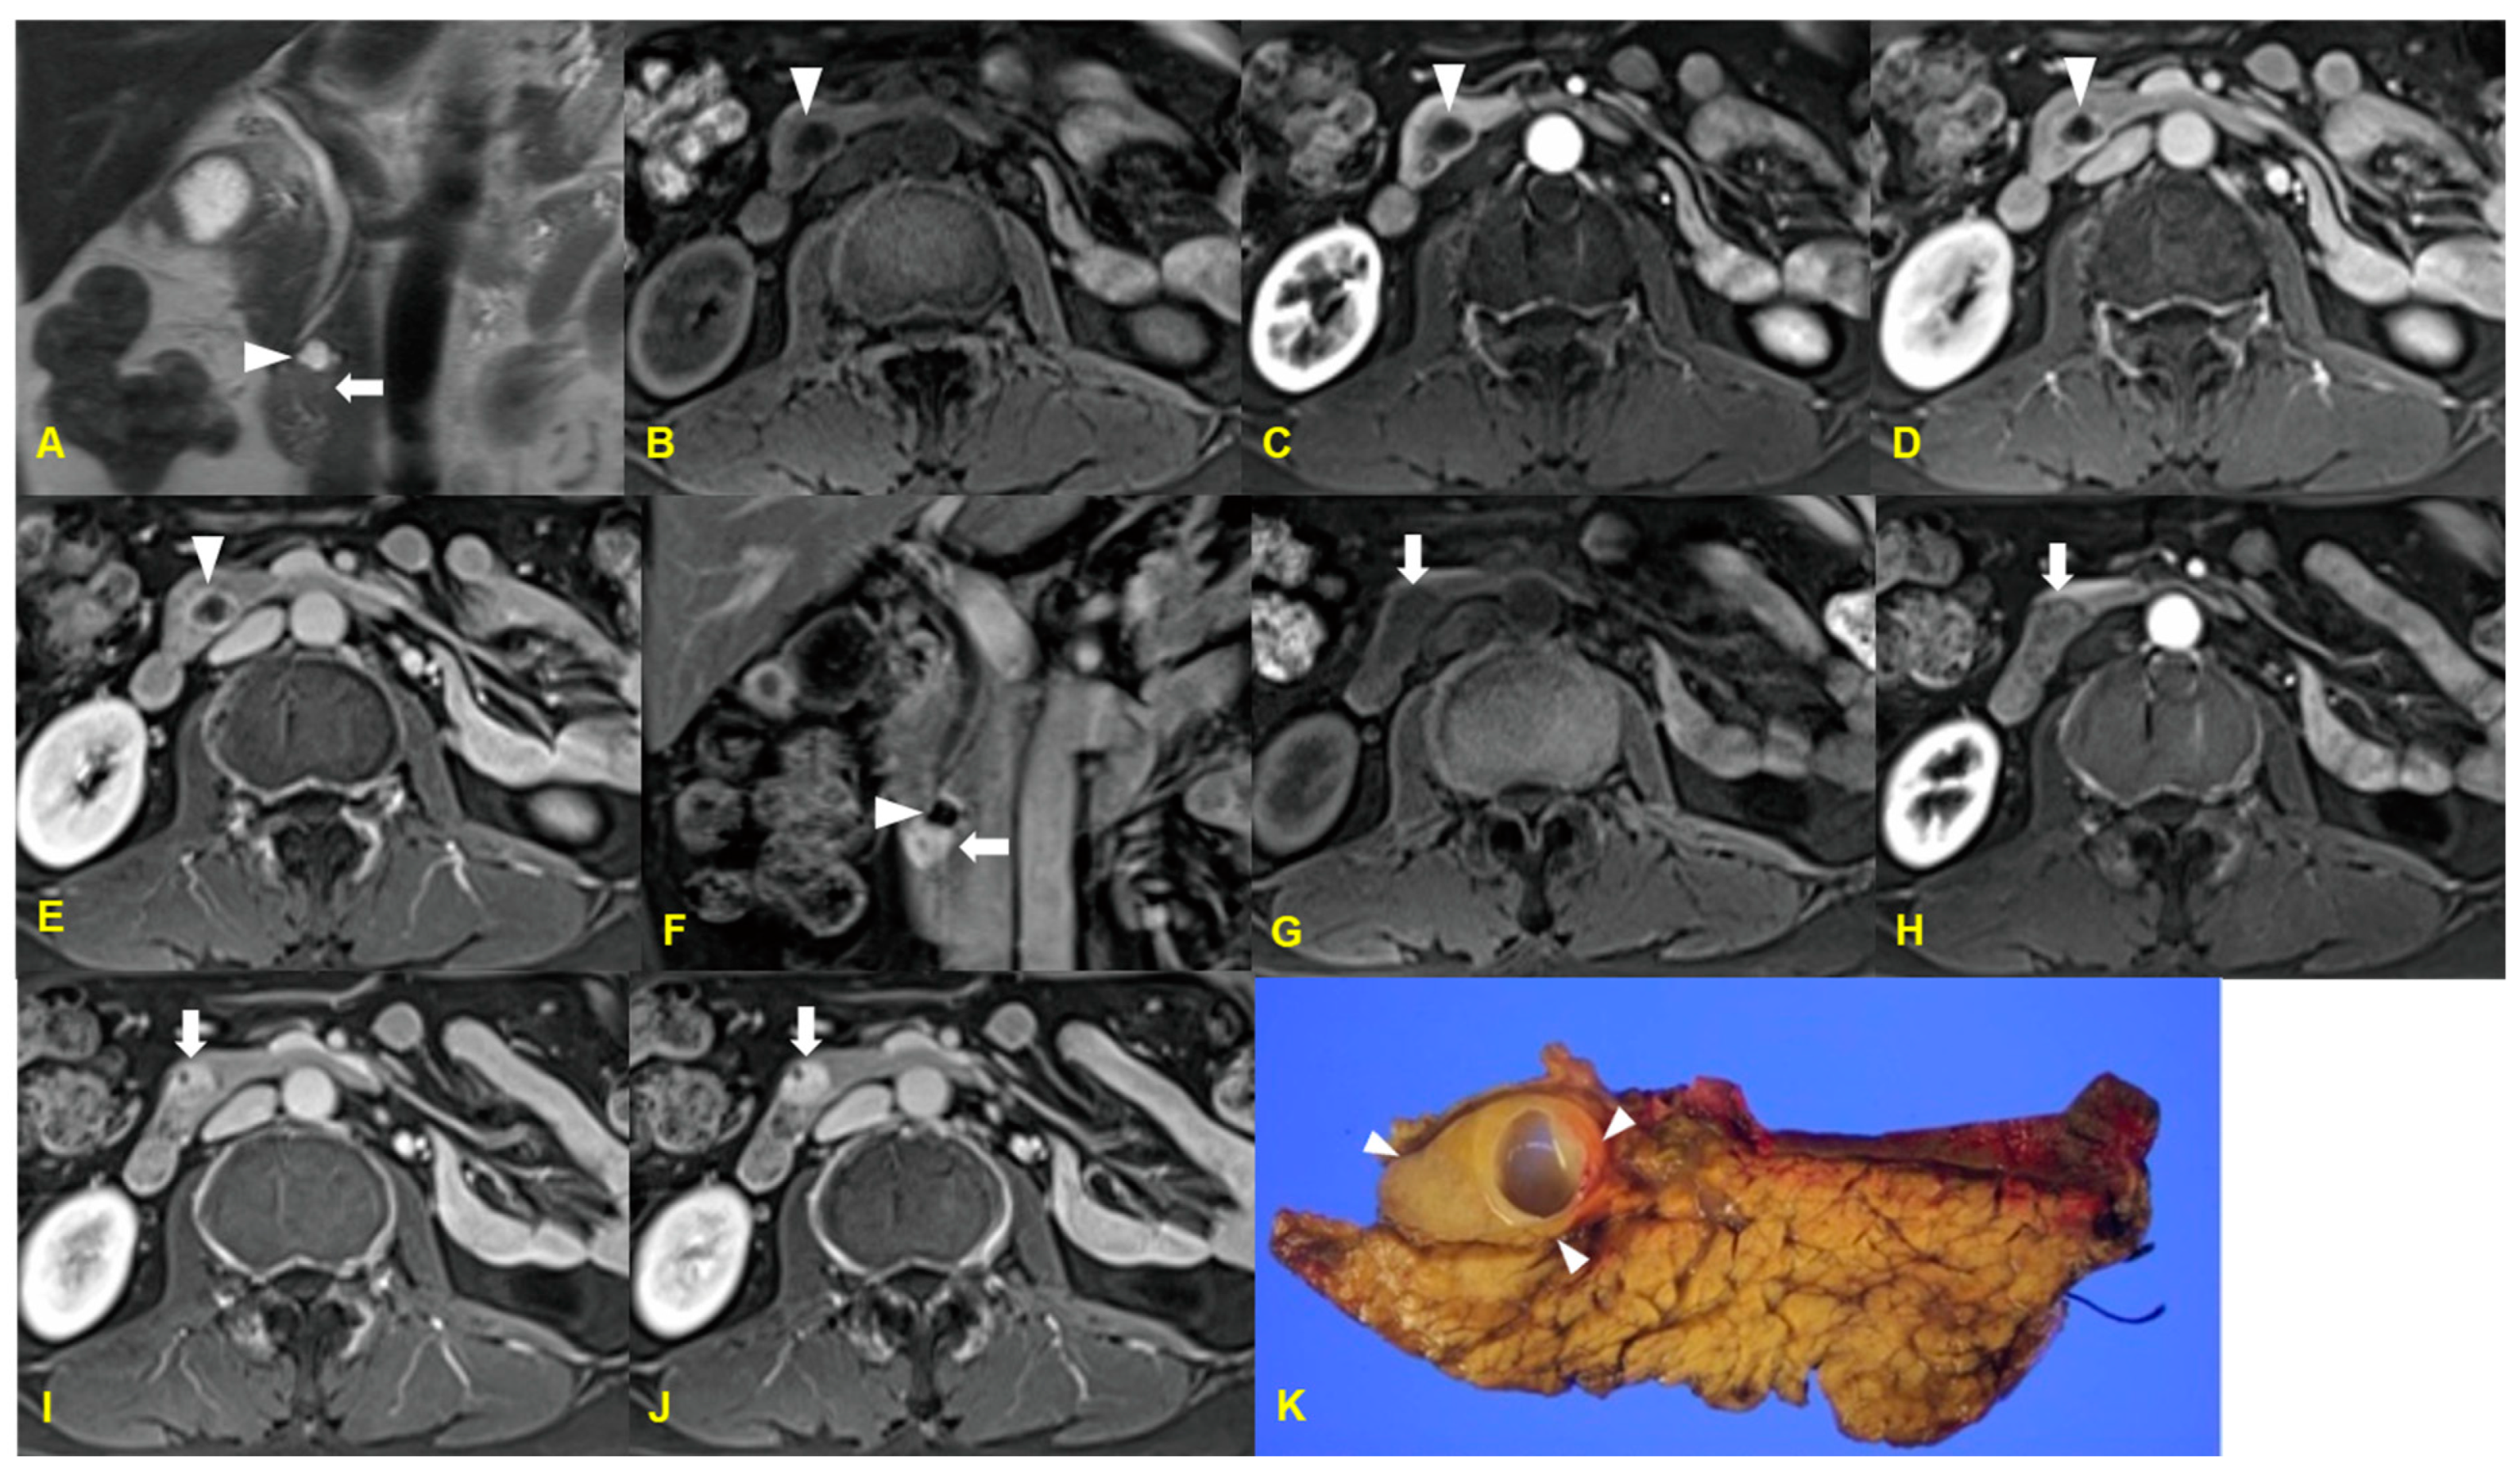

3. Acinar Cell Carcinoma

3.1. Imaging Finding

3.2. Differential Diagnosis

| Acinar cell carcinoma | Solitary/Exophytic and hypovascular mass with well-defined margin/Calcifications (frequent) |